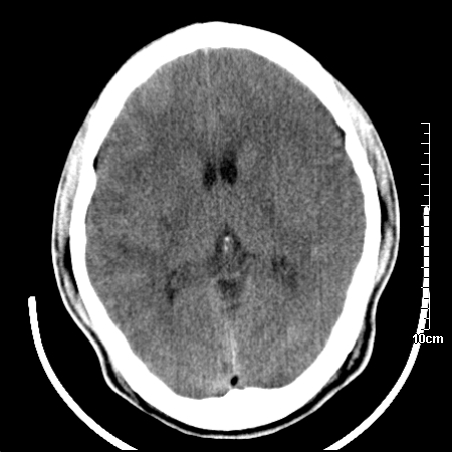

我当时诊断的是1.右侧底节区脑血栓形成

2.考虑少量蛛网膜下腔出血

3.右侧颞叶低密度区考虑脑血管畸形

因病人拒绝进一步检查,反复做工作后,病人做了腰穿,脑脊液化验显示有红细胞,呈现轻度红色

右侧基底节区低密度灶,建议磁共振检查。

右侧放射冠区混杂密度灶,边缘不清,病人较年轻,结合有发热病史,支持感染性病变,建议密切结合临床可抗感染治疗后复查。

右侧颞叶病变定性困难,既然发病急,又有发热,脑脓肿不能除外。

右侧颞叶混杂密度灶,强烈建议:增强ct检查